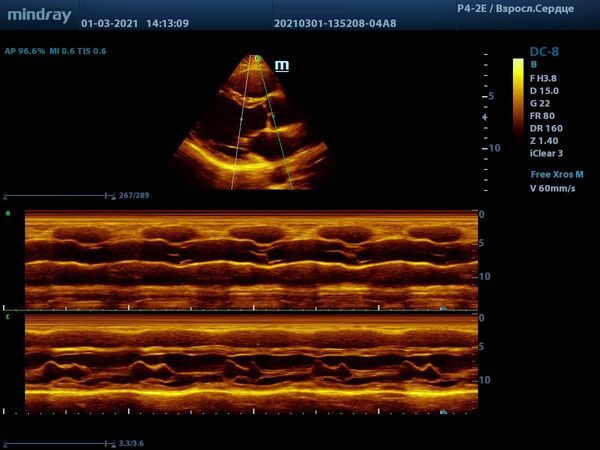

С М-режимом, первым из режимов эхокардиографии, знакомы все. Функцией свободного и анатомического М-режима активно пользуются обладатели машин высокого и экспертного класса. Эти функции используются для оценки створок митрального клапана, формы траектории их движения и амплитуды раскрытия, так же, как и для оценки синуса и полулуний аорты. Современные ультразвуковые диагностические системы компании Mindray, такой как экспертный прибор Mindray DC-8, способны проводить анализ в М-режиме сразу нескольких срезов до 3-х сечений за один раз. Больше не нужно отдельно выводить срез на уровне концов створок клапана и отдельно уровня синуса аорты. Всё получается нажатием пары кнопок и все готово к измерению.

Продвинутые операторы диагностической техники также владеют методами оценки функции желудочков в режиме Free Xros – свободном М-режиме. Такие параметры как TAPSE позволяют быстро и удобно оценить сократительную функцию правого желудочка, нормальное значение движения амплитуды кольца трикуспидального клапана 17 миллиметров или более.

Левый желудочек не остается в стороне, для него есть показатель MAPSE – измеряется в М-режиме и пересчитывается во фракцию выброса левого желудочка. Показатель более 10 мм считают нормой. Для расчета фракции необходимо подставить значение в формулу EF = 4.8 × MAPSE (mm) + 5.8. Такой способ оценки применяется только у взрослых. Использование нескольких срезов одновременно с функцией Free Xross позволит оценить сразу оба желудочка, что сильно экономит время и силы к концу трудового дня.